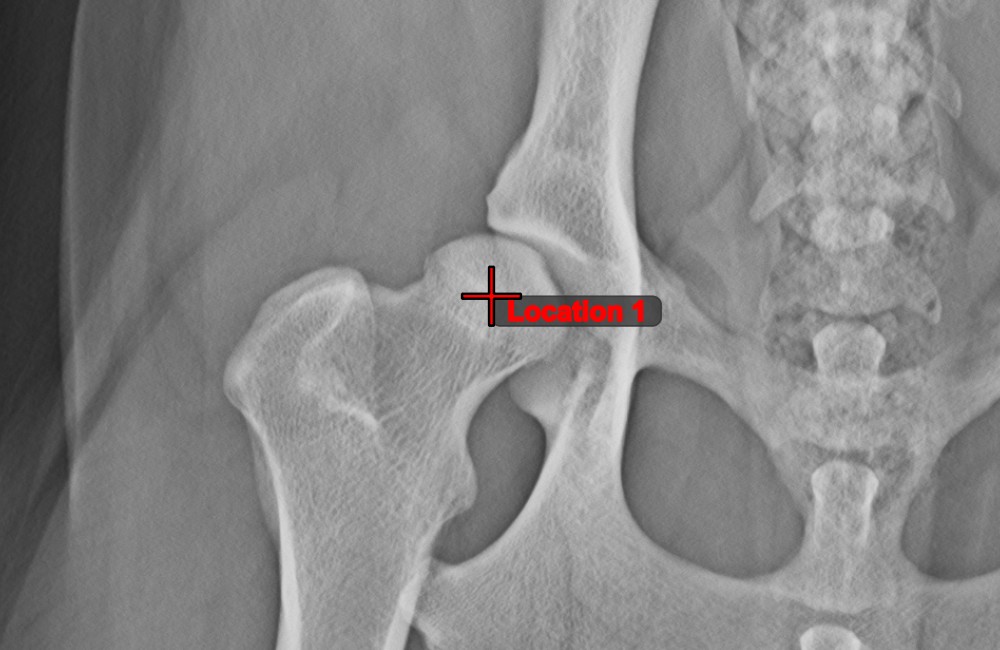

Text Tool¶

Label and comment important information on the image by using the Text Tool. The text is always assigned to a point that can be later modified by using the Select/Move Item tool.